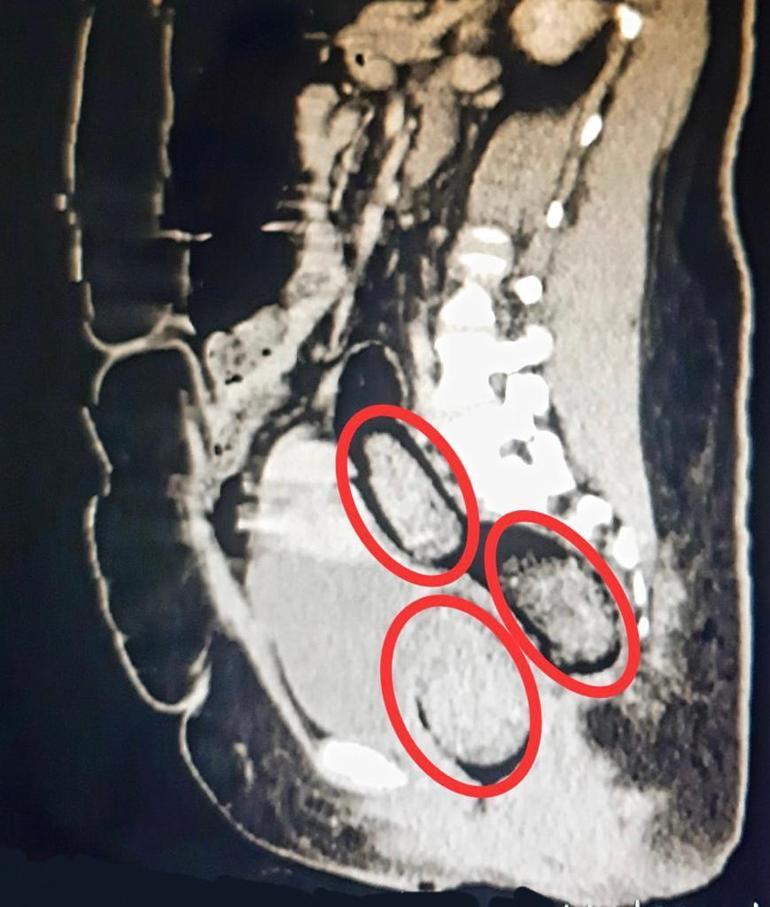

Kars Harakani Devlet Hastanesi'ne götürülen Aeınezad'ın çekilen röntgeninde, makatında uyuşturucu tespit edildi. Cerrahi operasyonla kadının makatından 3 parça halinde toplam 318 gram metamfetamin çıkarıldı. Emniyetteki işlemlerinin ardından adliyeye sevk edilen şüpheli, çıkarıldığı hakimlik tarafından tutuklandı.